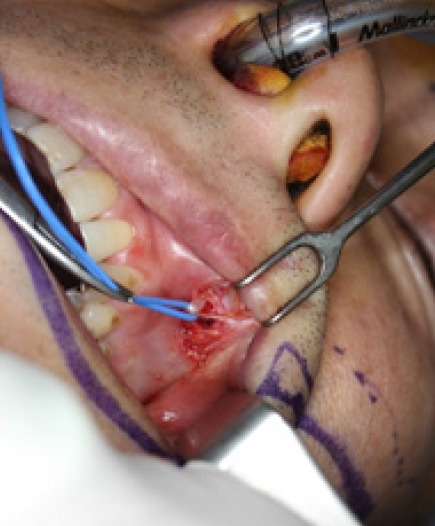

面神经刺激面部表情肌和面部副交感神经。因此,面神经麻痹会导致面部不对称、变形和功能障碍。面神经麻痹最常见的是特发性的,如贝尔麻痹,但也可能由肿瘤或外伤引起。本文将讨论外伤性面神经损伤。要确定损伤的原因,首先要确定损伤的位置。损伤的位置和程度决定了治疗方法,包括初次修复、神经移植、交叉面神经移植、神经交叉和肌肉转移。由于颞骨的复杂性,颅内近端面神经损伤给手术方法带来了挑战。这些病例的手术干预需要神经外科和耳鼻喉科的合作,而神经修复或移植是很困难的。本文介绍了周围面神经损伤的治疗方法。初次修复一般可获得最佳预后。如果在受伤后 6 个月内无法进行初次修复,则应尝试神经移植;如果超过 12 个月,则应进行功能性肌肉转移。如果当时无法使用受影响的神经,则可使用对侧面神经、同侧颌下神经或舌下神经作为供体神经。要成功治疗面神经损伤,还必须考虑其他伴随症状,如眼睑下垂或面中部下垂。

The facial nerve stimulates the muscles of facial expression and the parasympathetic nerves of the face. Consequently, facial nerve paralysis can lead to facial asymmetry, deformation, and functional impairment. Facial nerve palsy is most commonly idiopathic, as with Bell palsy, but it can also result from a tumor or trauma. In this article, we discuss traumatic facial nerve injury. To identify the cause of the injury, it is important to first determine its location. The location and extent of the damage inform the treatment method, with options including primary repair, nerve graft, cross-face nerve graft, nerve crossover, and muscle transfer. Intracranial proximal facial nerve injuries present a challenge to surgical approaches due to the complexity of the temporal bone. Surgical intervention in these cases requires a collaborative approach between neurosurgery and otolaryngology, and nerve repair or grafting is difficult. This article describes the treatment of peripheral facial nerve injury. Primary repair generally offers the best prognosis. If primary repair is not feasible within 6 months of injury, nerve grafting should be attempted, and if more than 12 months have elapsed, functional muscle transfer should be performed. If the affected nerve cannot be utilized at that time, the contralateral facial nerve, ipsilateral masseter nerve, or hypoglossal nerve can serve as the donor nerve. Other accompanying symptoms, such as lagophthalmos or midface ptosis, must also be considered for the successful treatment of facial nerve injury.